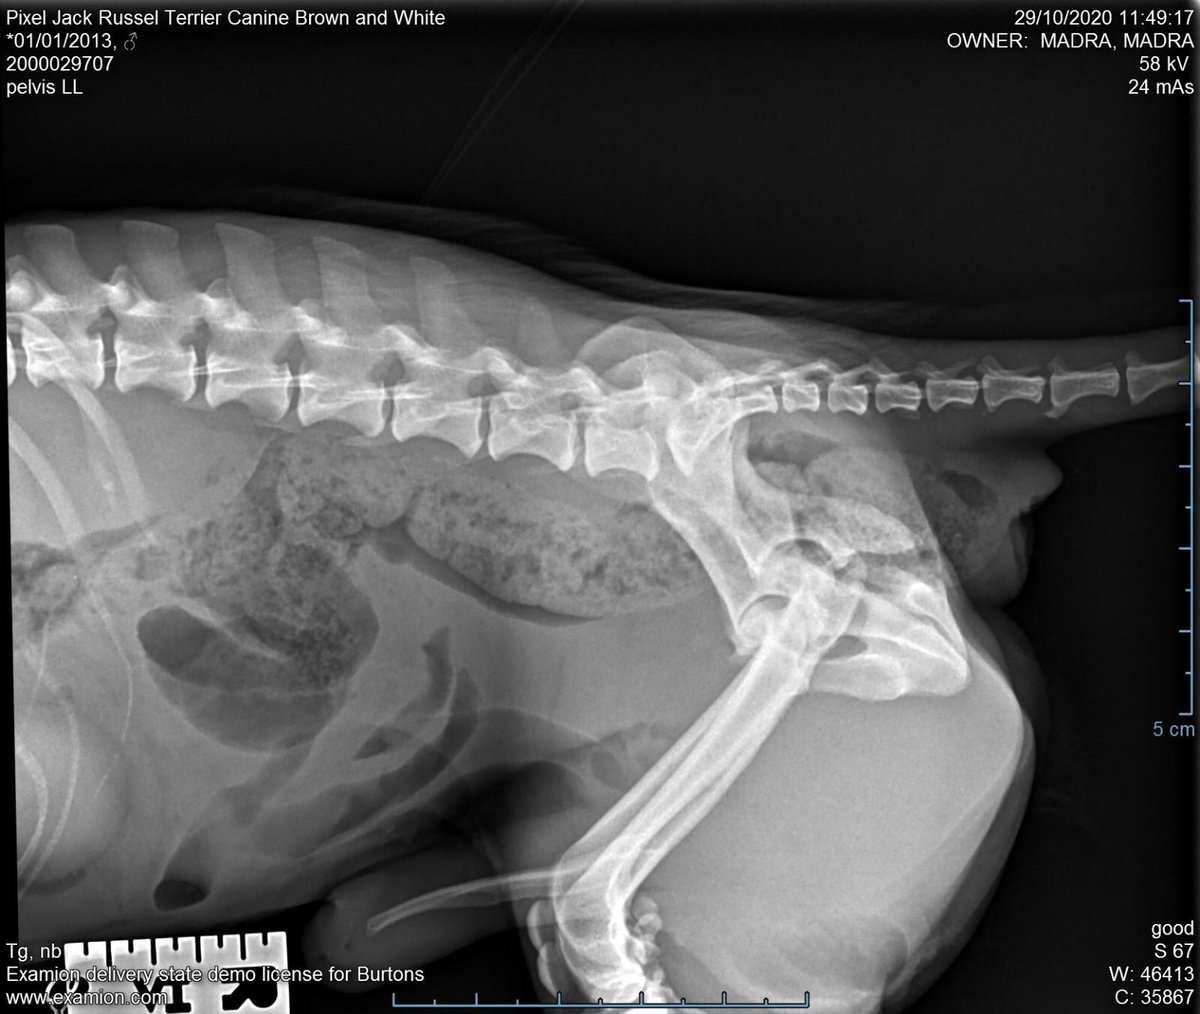

Of these eight dogs, four (Pierre, Pixel, Delilah and Blue) have pelvic or hindlimb fractures which were not treated initially....1/6 ImageImageImageImage

Orion has a suspected dislocated shoulder, Sandy has a forelimb injury or deformity and Ziggy and Davey have lameness which are being assessed.

Delilah and Orion need surgery while others will need ongoing monitoring, pain relief and/or physio.